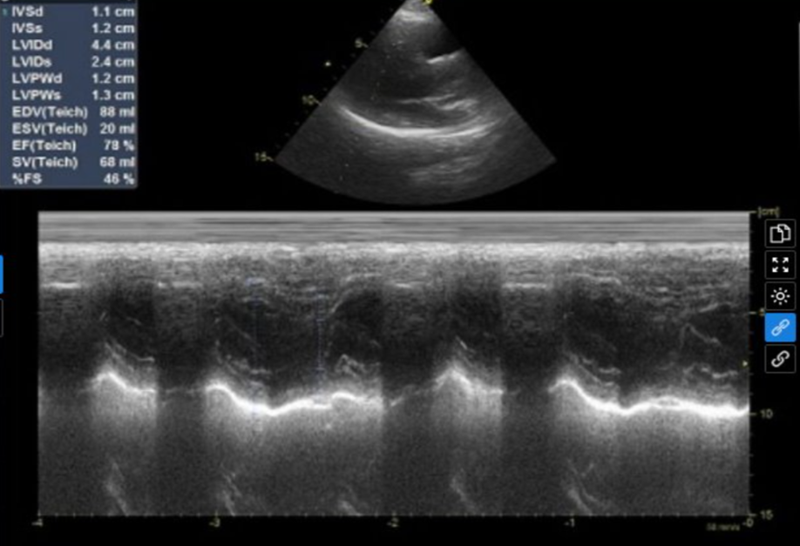

Kết quả siêu âm tim và màng phổi của bệnh nhân

Kết quả siêu âm tim và màng phổi cho thấy: tim lệch phải do tràn khí màng phổi mức độ nhiều; mất dấu trượt màng phổi, mất đường lines B; kích thước các buồng tim bình thường; chức năng tâm thu thất trái bình thường; không tăng áp lực động mạch phổi.